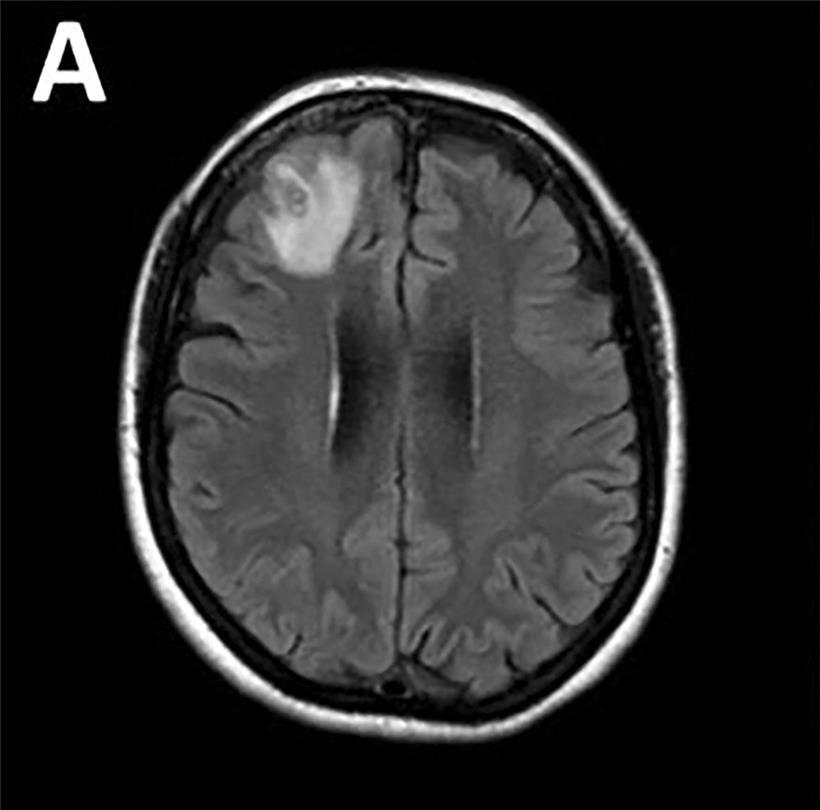

Ende Januar 2021 wurde die Patientin erstmals ins örtliche Krankenhaus eingewiesen. Zu dem Zeitpunkt hatte sie drei Wochen lang unter Bauchschmerzen und Durchfall gelitten, gefolgt von ständigem trockenen Husten, Fieber und nächtlichen Schweißausbrüchen. 2022 – also ein Jahr später – begann sie schließlich, subtile Veränderungen im Gedächtnis und in der Gedankenverarbeitung zu bemerken. Sie litt unter Vergesslichkeit und Depressionen. Die Patientin wurde zu einer Kernspintomografie des Gehirns geschickt, die letztendlich eine atypische Läsion im rechten Frontallappen des Gehirns zeigte.

Kernspintomografie des Gehirns zeigte eine atypische Läsion im rechten Frontallappen

Kernspintomografie des Gehirns zeigte eine atypische Läsion im rechten Frontallappen Foto: AFP/The Australian National University